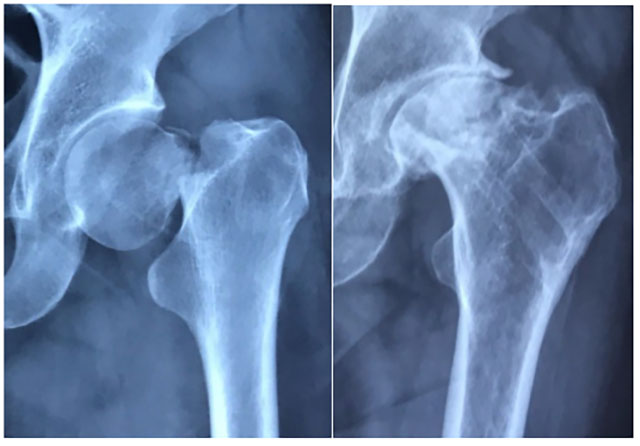

什么是股骨颈骨折?

股骨颈是股骨头和股骨粗隆之间连接的较细的部分。

股骨颈骨折是髋部最常见的骨折,中老年人多见。中青年人股骨颈骨折也逐年上升,骨折后易出现骨不愈合、骨坏死造成较高的致残率。

为什么说股骨颈骨折更难愈合?

1.特殊血供结构